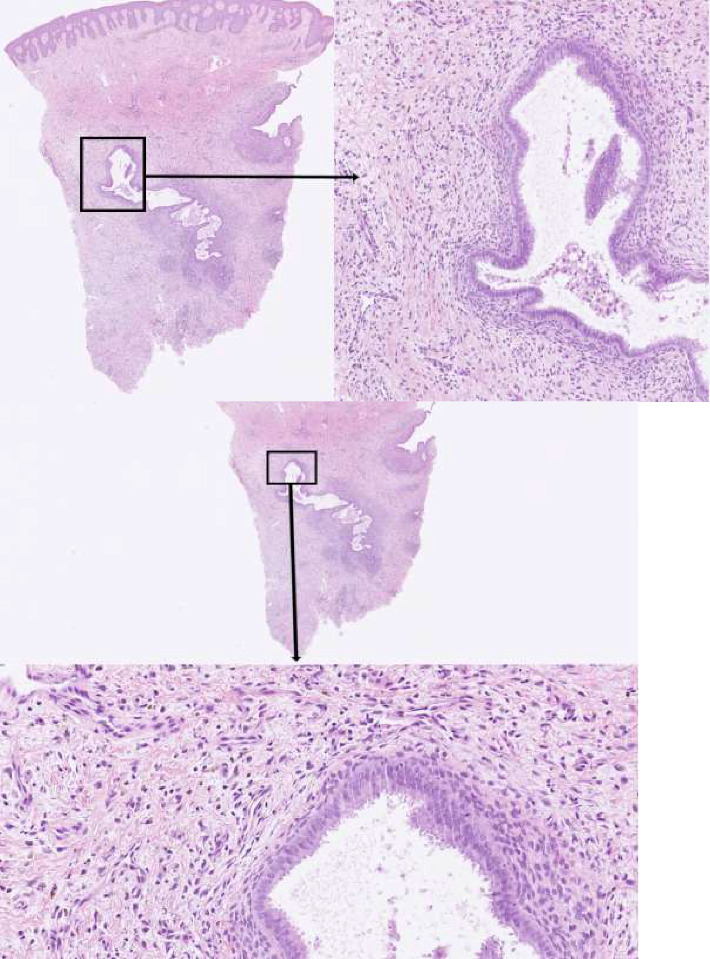

皮肤子宫内膜异位症是一种罕见的子宫内膜异位症的表现,其皮肤镜特征的报道很少发表。在这个病例报告中,我们提出了一个40岁的女性皮肤子宫内膜异位症,出现在剖腹产疤痕,表现出独特的皮肤镜特征。患者表现为瘢痕右端结节状、乳头状瘤样生长,皮肤镜检查显示无结构的红色乳头状瘤突起,以及白色网状网络包围的红色点状血管的非乳头状瘤区。活检证实诊断为子宫内膜异位症。据我们所知,这是第一次报道这种皮肤镜特征的皮肤子宫内膜异位症引起的剖腹产疤痕。我们的病例报告增加了目前有限的皮肤镜特征的皮肤子宫内膜异位症的知识,可能有助于这种情况的诊断。

Cutaneous endometriosis is a rare manifestation of endometriosis, and few reports on its dermoscopic features have been published. In this case report, we present a 40-year-old female with cutaneous endometriosis arising in a caesarean scar, exhibiting unique and distinct dermoscopic features. The patient presented with a nodular, papillomatous growth in the right end of the scar, and dermoscopic examination revealed structureless red papillomatous projections, as well as nonpapillomatous areas with red dotted vessels surrounded by a white reticular network. A biopsy confirmed the diagnosis of endometriosis. To our knowledge, this is the first report of such dermoscopic features in cutaneous endometriosis arising in a caesarean scar. Our case report adds to the current limited knowledge of dermoscopic features of cutaneous endometriosis and may help in the diagnosis of this condition.